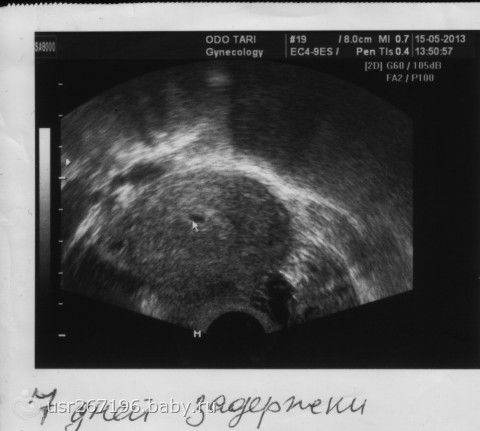

а вот мы… разница в 9 дней всего, а по фото не скажешь....